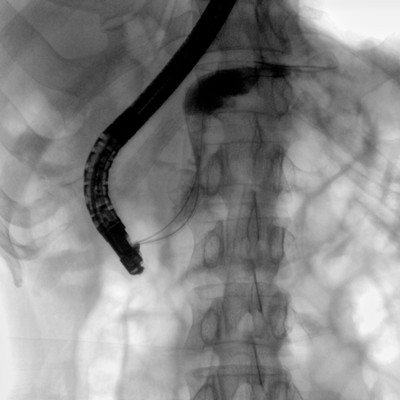

消化內(nèi)科: ERCP、PTCD、肝臟介入(TACE、灌注)、食管支架等。

優(yōu)質(zhì)平板探測(cè)器、可靈活升降調(diào)節(jié)SID、獨(dú)特圖像處理系統(tǒng)、高品質(zhì)濾線柵,大視野成像清晰不失真。

采用智能劑量控制技術(shù),可根據(jù)不同體型和不同部位,準(zhǔn)確調(diào)節(jié)投照劑量。使操作者在任何使用環(huán)境下,都能實(shí)現(xiàn)低劑量、診視圖像清晰的效果。

采用電動(dòng)機(jī)架設(shè)計(jì),可以實(shí)現(xiàn)C形臂繞水平軸旋轉(zhuǎn)、沿弧滑動(dòng)、上下升降、 水平延伸四方向電動(dòng)運(yùn)動(dòng),充分滿足臨床擺位需求。